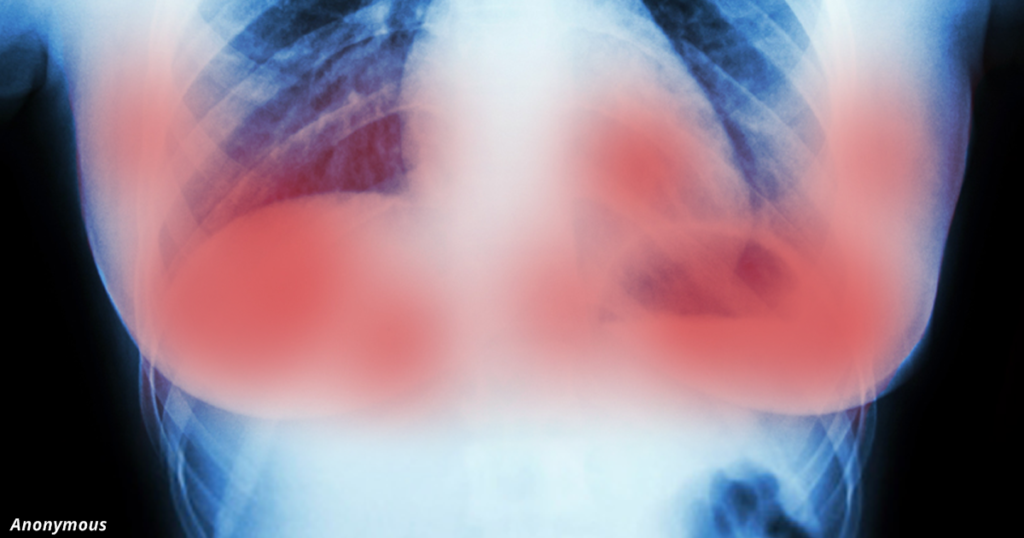

На Европейской конференции онкологии груди были представлены результаты работы голландских учёных, которые успешно применили комбинацию препаратов герцептина (трастузумаба) и лапатиниба для лечения рака молочной железы.

В сочетании эти препараты уничтожают конкретный белок — рецептор эпидермального фактора роста человека (HER2) — который влияет на развитие и размножение раковых клеток. Этот тип рака также опасен рецидивами.